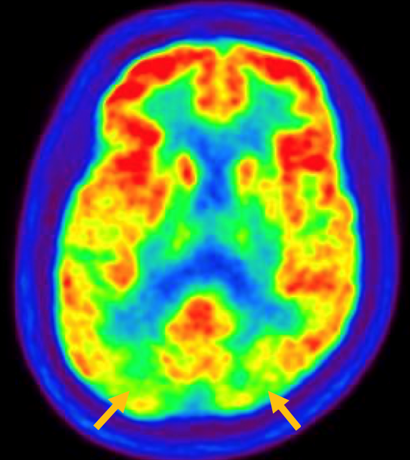

피질 기저핵 변성은 비대칭 증상을 두드러지게 보인다는 점에서 파킨슨병과 비슷합니다. 그러나 파킨슨병과 비교해 보았을 때 양측의 차이가 아주 심하게 나타난다는 특징이 있습니다. 질병 초기에 한쪽 손으로 동작을 하거나 계획된 행동을 하는 기능이 현저하게 떨어집니다. 간단한 손가락 모양도 따라 하지 못하는 현상을 보입니다. 또한 의지와 상관없이 제멋대로 움직이는 통제불능 손이 나타날 수 있습니다. 체위 떨림, 경축, 운동 완만과 같은 파킨슨병에서 볼 수 있는 증상들은 피질 기저핵 변성에서도 관찰될 수 있습니다. 또한 집중력 장애, 수행 장애, 이름 대기나 언어의 유창성이 떨어지는 등 전두엽 및 두정엽과 관련된 인지 장애가 나타납니다. 피질 기저핵 변성은 뇌 자기공명영상(MRI)에서 증상의 반대쪽 전두두정엽의 위축 소견이 특징적으로 나타납니다. 뇌포도당 양전자 단층촬영(PET)에서도 전두엽, 뇌기저핵에 비대칭적인 대사 저하의 소견이 보입니다.

[피질기저핵 변성 환자의 뇌자기공명영상에서 확인되는 비대칭 뇌피질의 소견]

[피질기저핵 변성 환자의 뇌포도당 양전자 단층촬영에서 확인되는 비대칭적인 대사 기능 저하]4. 루이소체 치매(Dementia with Lewy bodies)